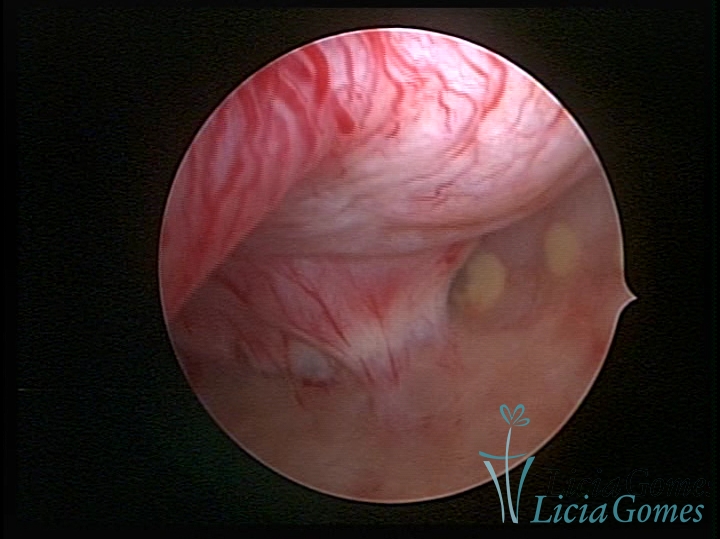

• SINÉQUIA TIPO FIBROMUSCULAR